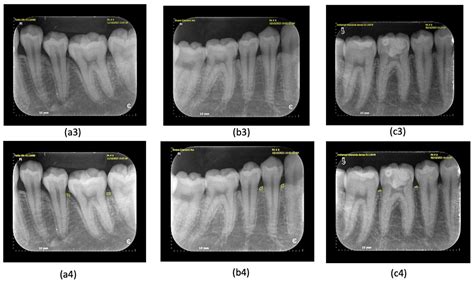

• Imaging tests (X-rays, MRI, CT scans) • Blood tests to check hormone levels • Biopsy to determine malignancy